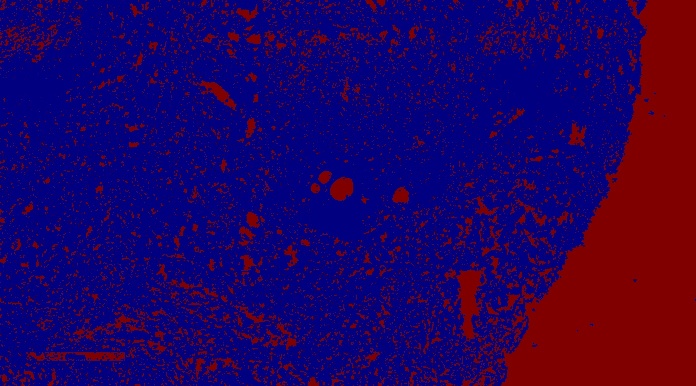

在这一点上,我想计算B细胞与未染色组织的面积之比。此操作提示根据颜色范围提取背景单元格层:

K=2的kmeans: